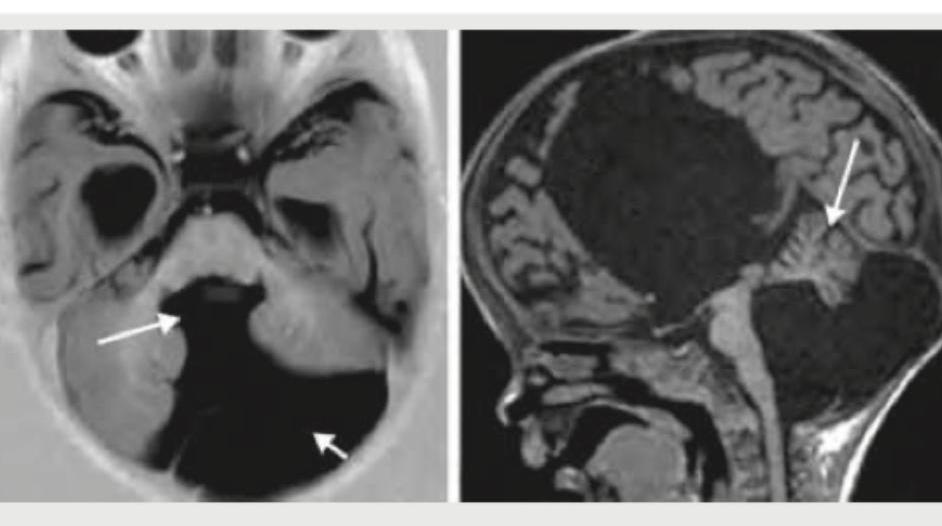

A 6-month-old child is on Vancomycin for pneumonia for 2 days. He develops worsening of respiratory distress and $\mathrm{SpO}_{2}$ falls to $80 \%$. The CXR performed is shown below. What is the diagnosis?

Explanation: ***Pneumothorax*** - The CXR shows marked hyperlucency and absent lung markings on the right side, along with a collapsed lung (seen as a dense shadow centrally), characteristic of a **pneumothorax**. - Worsening respiratory distress and a significant drop in saturation in a child with pneumonia receiving vancomycin (suggesting severe infection) could indicate a complication like a tension pneumothorax, which requires urgent intervention. *Lung abscess* - A lung abscess typically appears as a **cavitated lesion** with an air-fluid level, usually within the lung parenchyma. - While pneumonia can lead to abscess formation, the CXR image does not show a circumscribed cavitary lesion but rather a generalized collapse of lung tissue. *Empyema* - Empyema is characterized by **pus in the pleural space** and would typically manifest as a **pleural effusion** with a fluid level when erect, or diffuse opacification of the hemithorax. - The image distinctly shows a clear space with absent lung markings and a displaced lung, which is not consistent with merely fluid accumulation. *Segmental collapse* - **Segmental collapse (atelectasis)** would appear as an area of **increased density** within the lung itself, with crowding of vessels and bronchi, and possibly displacement of fissures and mediastinum towards the affected side. - This is distinct from the hyperlucent appearance of the right hemithorax and the clear displacement of the lung boundary seen in the image.